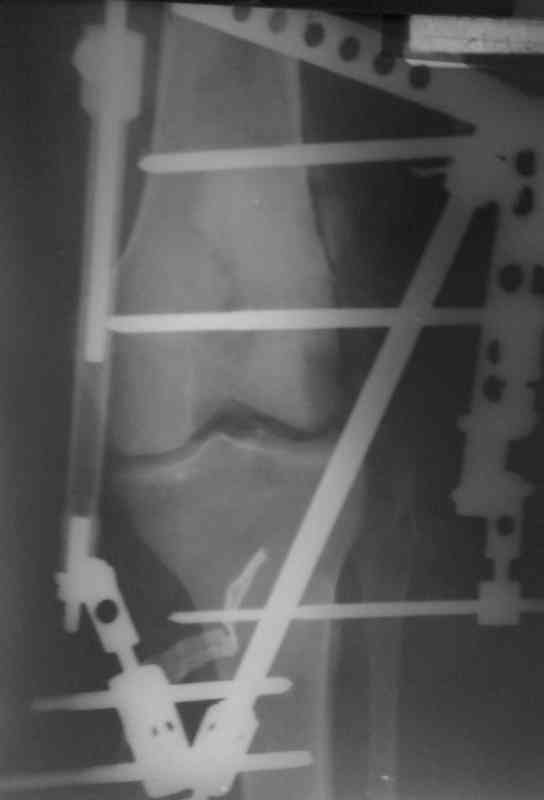

Аппарат внешней фиксации удаляется в 6-7 недель,

предпочтительно под общим обезболиванием, во время

удаления проверяется стабильность и амплитуда движения в коленном суставе с редрессацией.

Последующее два-три месяцев проводим ЛФК сустава,

потом на основании стабильности сустава решается

необходимость оперативного вмешательства.

Общепринятые последовательности реконструкции,

поэтапные восстановление PCL плюс медиальная или PCL плюс латеральная, хотя множество случаев когда связки срастались в течение 6-7 недель, больные восстанавливали движения сустава без оперативного вмещательства.

Снимки прошлых публикации из моего Power point